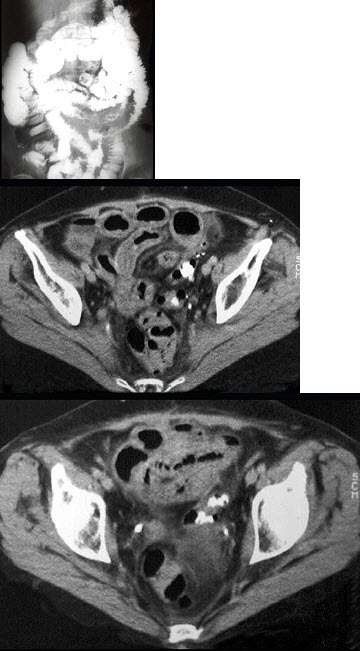

男,55岁,腹部胀痛不适一月余,CT检查如图,最可能的诊断是( )

A:结肠结核

B:结肠淋巴瘤

C:结肠转移瘤

D:假膜性结肠炎

E:横结肠癌